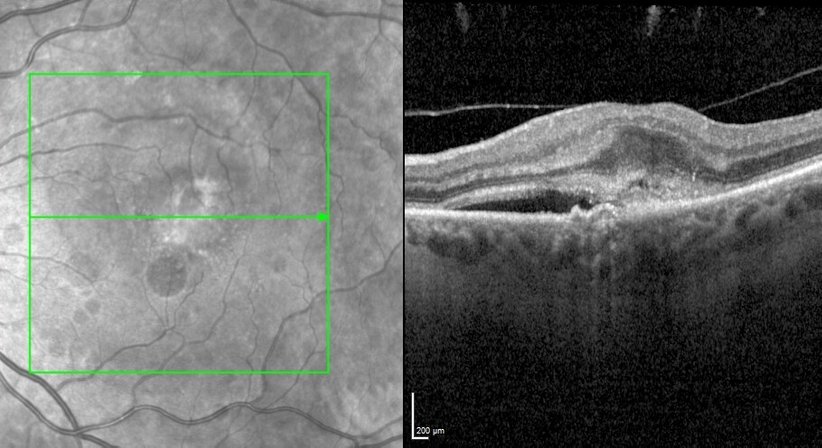

Erkrankungen der Makula kann der Augenarzt mittels eines Mikroskops (sog. Funduskopie) und unterstützend mittels einer hochauflösenden Laser-Schichtbildaufnahme (sog. OCT, optische Kohärenz Tomographie) des Netzhautgewebes diagnostizieren, beurteilen und kontrollieren. Vor allem bei Diabetikern und Patienten mit altersbedingten Netzhauterkrankungen (z.B. altersbedingte Makuladegeneration oder feuchte AMD) sollten regelmäßige Kontrollen der Netzhaut durchgeführt werden. Wir bieten unseren Patienten auch zur Vorsorge hochauflösende OCT-Untersuchungen der Makula an.